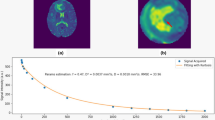

From the seven included patients, two had a high-grade and five a low-grade glioma. Patient characteristics are provided in Table 2. Perfusion was high in glioblastoma and low in all low-grade tumours, as expected. The rCBV histograms, mean, median and maximum values are given in Fig. 1.

DSC perfusion MRI has demonstrated a powerful role in neuroradiology practice to clinically and non-invasively assess the histopathological features and vascular characteristics of brain tumours [5, 7, 12, 26]. The rCBV parameter derived from DSC perfusion MRI has been used to differentiate between tumour grades on the basis of the tumour vascularity, where increased malignancy is associated with increased vascularity [12, 27, 28]. Maia et al. [28] evaluated the correlation between rCBV and tumour angiogenesis in glioma using the vascular endothelial growth factor (VEGF) as a marker for angiogenesis. Their results showed that high-grade tumours had a positive VEGF immunoreactivity and significantly correlated to high rCBV values, compared to low-grade tumours with no VEGF expression with low values of rCBV. Furthermore, the study of Huang et al. [29] measured the expression of VEGF and its receptors in different types of brain tumours. Their findings demonstrated that glioblastoma has the highest amount of VEGF protein with high expression of the receptors VEGFR-1 and VEGFR-2 m-RNA that majorly contribute to the high vascular density and angiogenesis of glioblastoma. In accordance with these results, our rCBV maps for glioblastoma showed a high perfusion value of (3.1) compared to high-grade astrocytoma grade 4 with an rCBV value of (1.2). Additionally, Law et al. [30] assessed the sensitivity and specificity of DSC perfusion MRI in grading glioma compared to the conventional MRI, reporting 95% sensitivity and 57.5% specificity with a threshold value of 1.7 for the rCBV ratio. In accordance with these findings, we found that all low-grade glioma in our cohort had an rCBV ratio of < 1.7.

Despite the common use of rCBV in clinical practice to assess tumour grade, this perfusion-derived parameter might still be inaccurate with sensitivity ranging from 55 to 83%, especially in cases of oligodendroglioma [30, 34]. Lev et al. [34] demonstrated in their study that glioma grading using rCBV might be inaccurate when oligodendroglioma is included. Moreover, oligodendroglioma showed high perfusion on rCBV maps not reflective of the histological grading. While this may explain part of the less-than-perfect accuracy of DSC perfusion MRI for tumour grading, we should also consider technical aspects. The assessment of the tumour vascularity using DSC perfusion MRI in the previously published studies relies on the assumption of arbitrary random orientation of vessels with uniform distribution [35, 36]. This is in discrepancy to our observations from the intraoperative ultrafast Doppler ultrasound images, in which we have seen that the tumour vascularity varies in the different histopathological and molecular types of glioma, ranging from a dense transversal compact network to well-structured arraying vessels. The estimation of rCBV in brain tumours may thus be inaccurate, and this may be more pronounced in certain tumour types than others depending on their microvascular architecture. Thus, future work is warranted to optimise the estimation of rCBV for grading and typing glioma by using ultrafast Doppler ultrasound images and to investigate the influence of vessel geometry on the estimation rCBV, while taking into consideration that the assumption of random oriented vessel might still be valid at the microscale level of 100 μm compared to the spatial resolution (200 μm) of the ultrafast Doppler ultrasound.